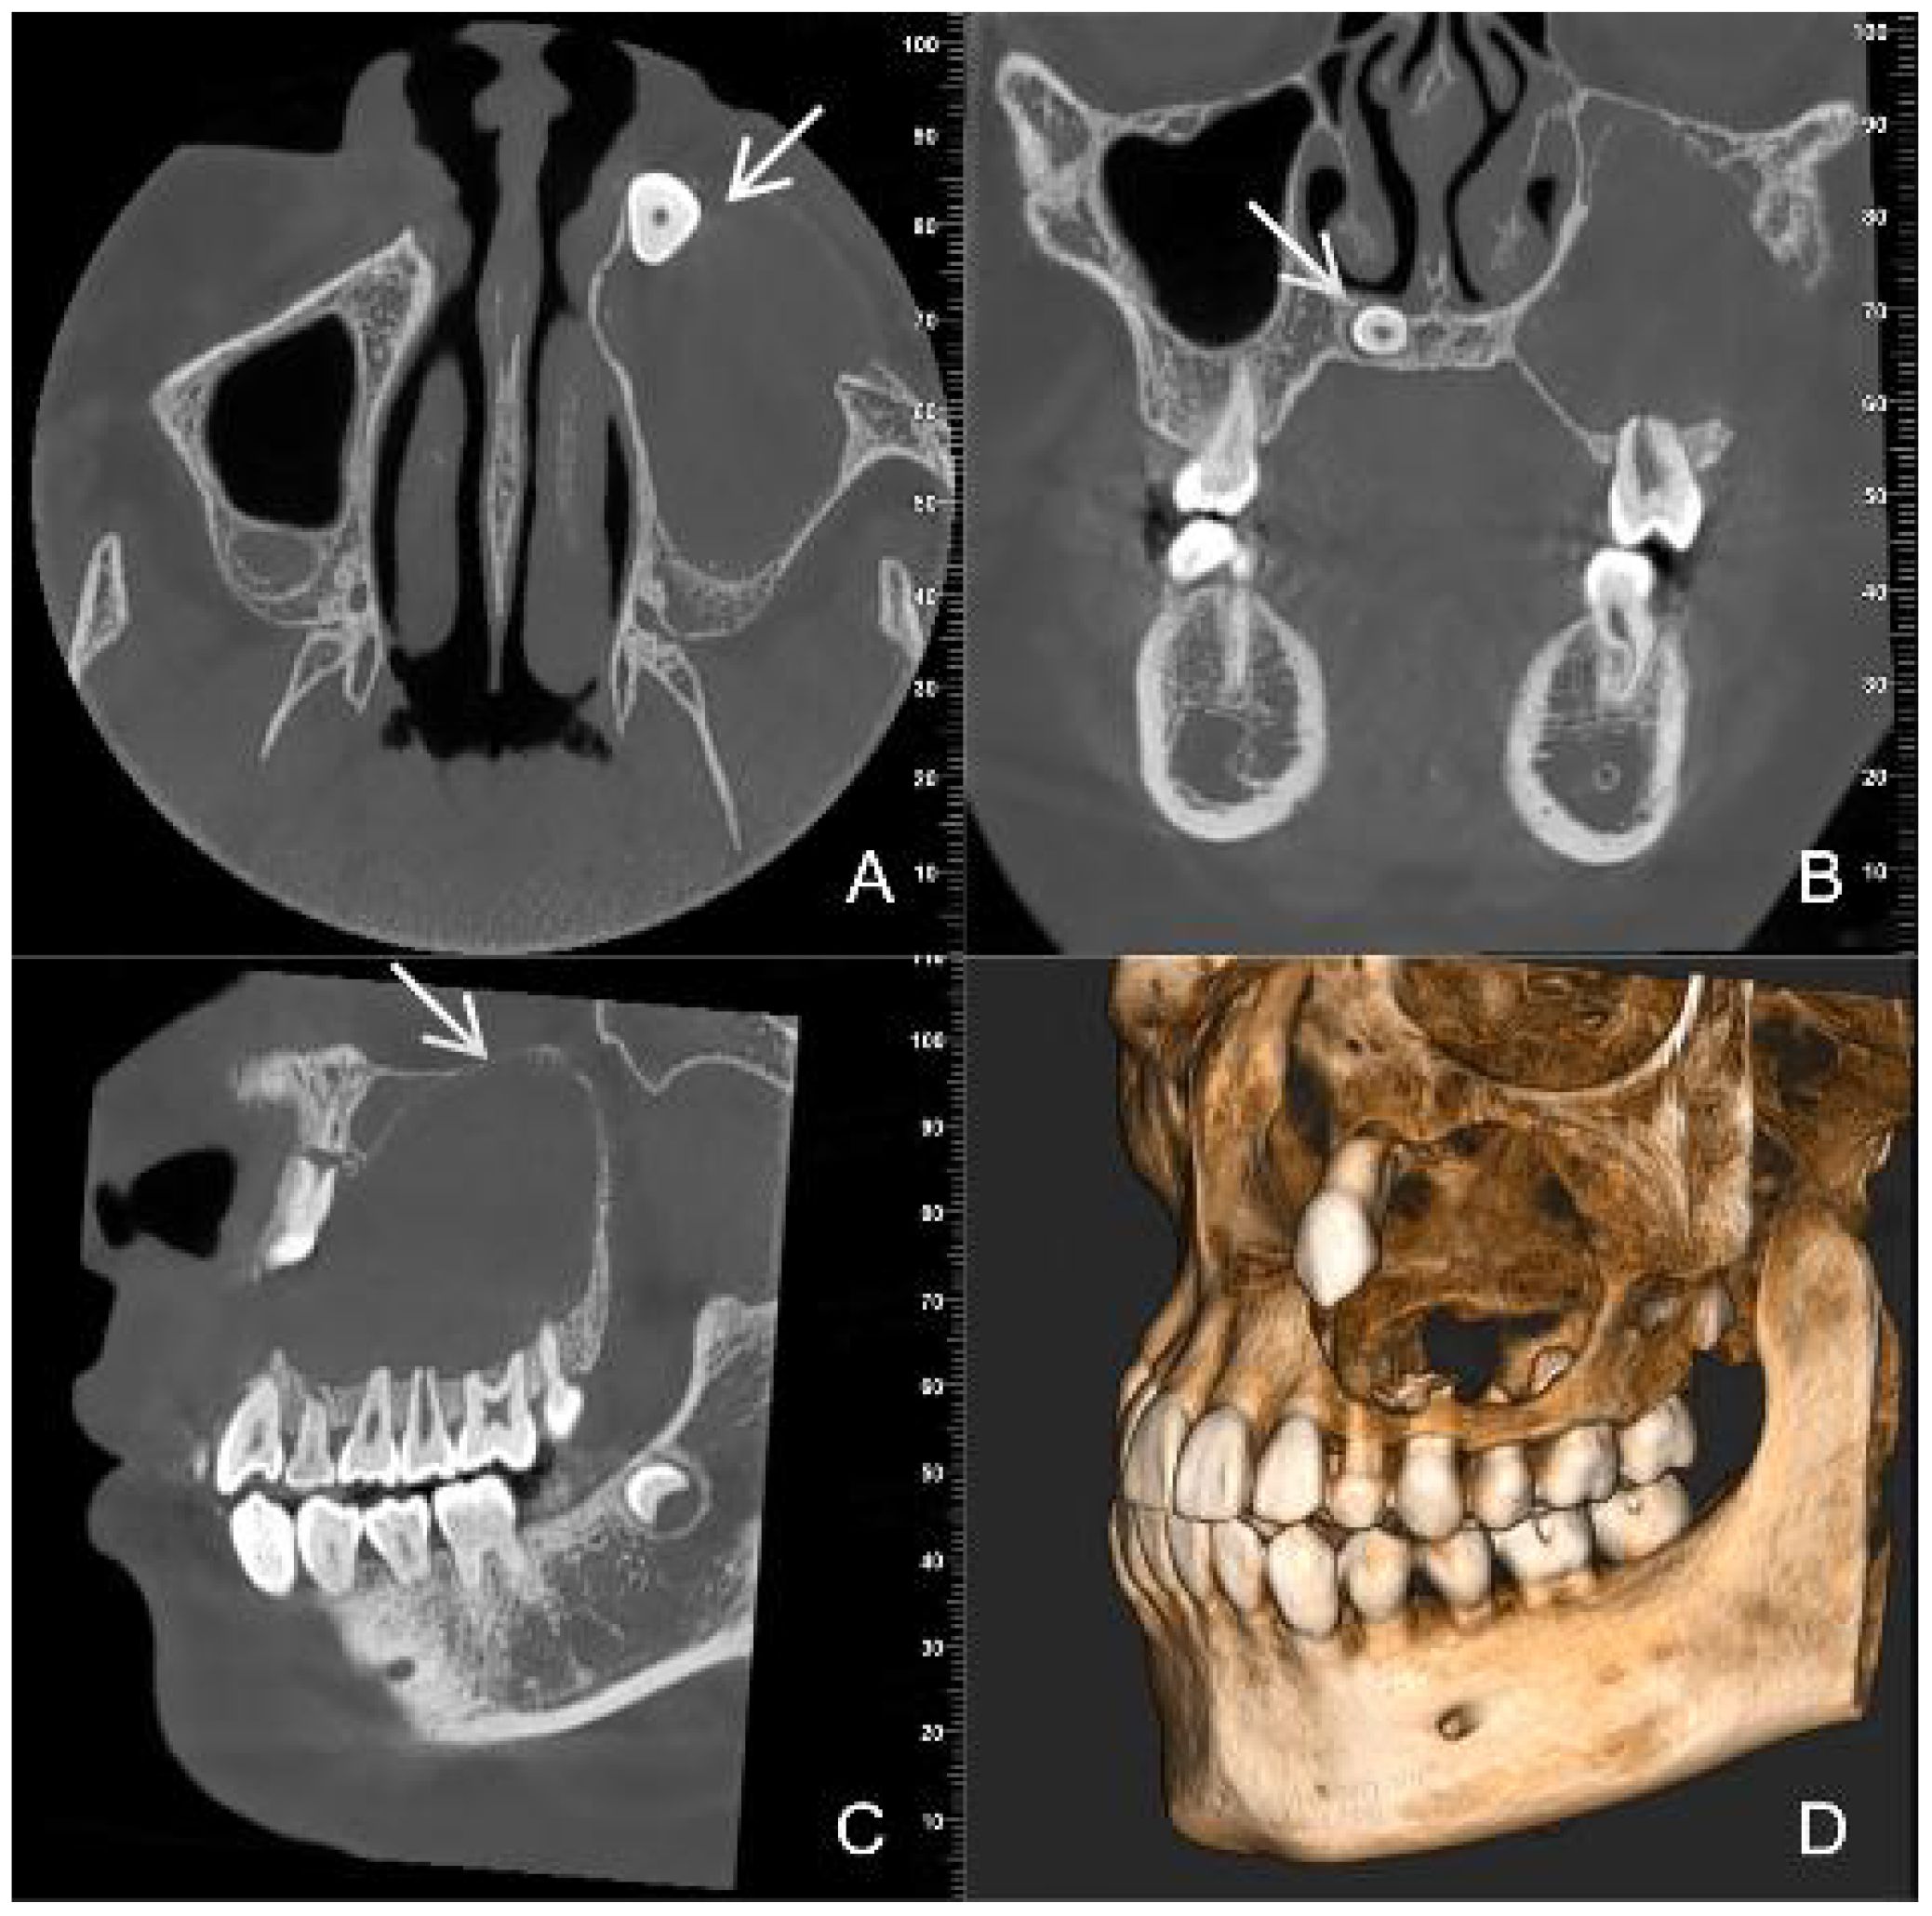

Dentinogenic ghost cell tumor (DGCT) is a rare odontogenic neoplasm that presents with nonspecific clinical manifestations and imaging features. It is more prevalent in elderly patients, with cases in children being extremely rare. This article presents a case study of a 10-year-old male patient who exhibited symptoms of swelling and pain in the left cheek for a duration of two weeks. Cone beam computed tomography (CBCT) demonstrated a hypodense lesion involving the left maxilla, with extension into the maxillary sinus and buccal cortical expansion. The patient underwent decompression, and histopathological examination of the intraoperative specimen suggested a diagnosis of calcifying odontogenic cyst (COC). One year after decompression, the patient underwent a tumor resection and the diagnosis of DGCT was confirmed by the post-operative pathology. Six months after tumor resection, CBCT showed complete bone remodelling in the lesion area. The patient is currently undergoing regular follow-up. This case provides an important reference for the diagnosis and treatment of pediatric DGCT, helping clinicians to develop individualised treatment plans.